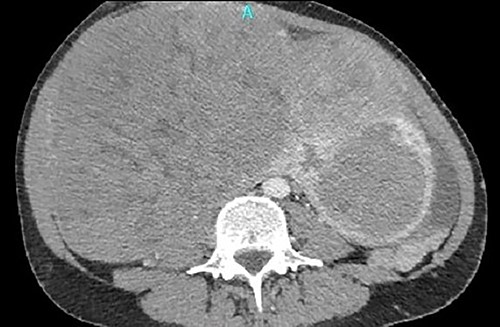

The macroscopic description reported a large compact solid mass with oblique perimeter with dimensions of 27 × 18 × 15.5 cm (Fig. 4). The microscopic examination reported a leiomyoma of uterus with vitreous degeneration, with mild to moderate lesions of cervicitis.